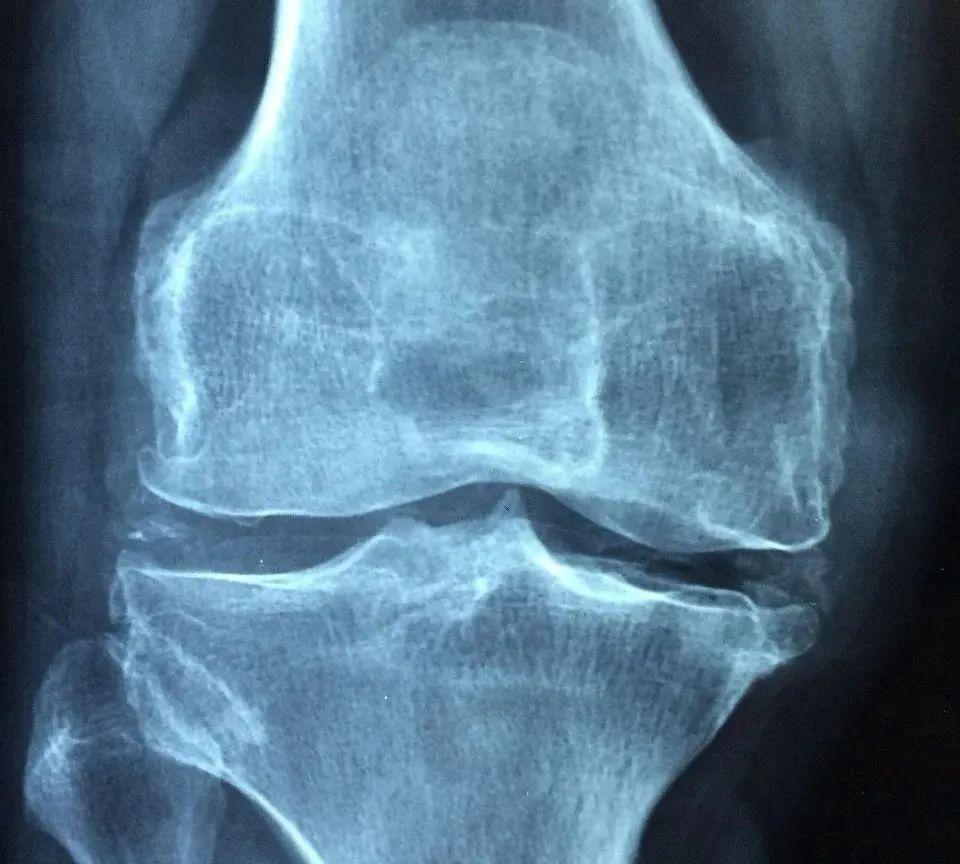

膝关节是人体最大、最复杂的关节之一,由股骨、胫骨和髌骨(也就是我们常说的膝盖骨)组成,周围有多条韧带、肌腱和肌肉共同维持其稳定性和灵活性。

6.关节炎

骨关节炎或类风湿性关节炎等慢性关节疾病也可能导致膝关节的稳定性下降,出现瞬间无力的情况。骨关节炎多见于老年人,而类风湿性关节炎则可发生于任何年龄段。

如果膝盖突然“软”一下的情况频繁发生,或者伴有疼痛、肿胀等症状,建议及时就医,进行详细的检查和诊断。医生可能会建议进行影像学检查以确定具体病因。